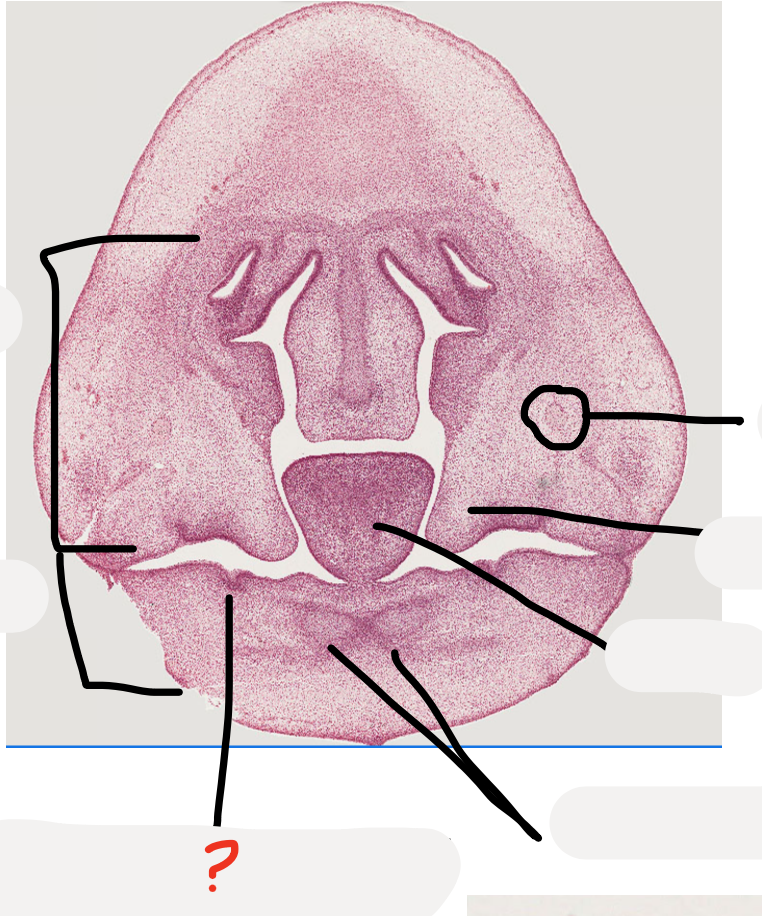

20

Q

A

nasal capsule

21

what age is this specimen? why?

Week 8, palatal shelves elevated but not fused yet

23

which forms first maxilla or mandible?

24

25

mandibular process

developing mandible

26

what is this structure at the base of the nasal capsule?

developing vomer dark cells are osteoblasts making bone

27

note this

28

what is this?

Nasal capsule is made up of cartilage -> nasal septum is part of it

29

what is this in the maxillary process?

maxillary nerve trunk

30

tooth germ

31

32

palatal shelves

33

34

meckel's cartilage

35

36

inferior alveolar nerve

37

this will be the sulcus

38

look at this inferior alveolar nerve next to the developing mandible